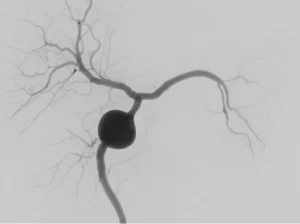

• Aneurisma Cerebral